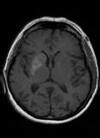

QUAL ACHADO TÍPICO DA RNM DA DOENÇA DE HUNTINGTON?

ATROFIA DO CAUDADO E PUTÂMEN

PACIENTE COM ESSA RNM + DM PENSAR EM QUAL DISTURBIO DO MOVIMENTO?

COREIA METABÓLICA - HIPERGLICEMIA NÃO CETÓTICA TC: HIPERDENSIDADE ESTRIATAL RNM: HIPERSINAL NO T1 c/ t2 e flair variáveis (geralmente hipo)